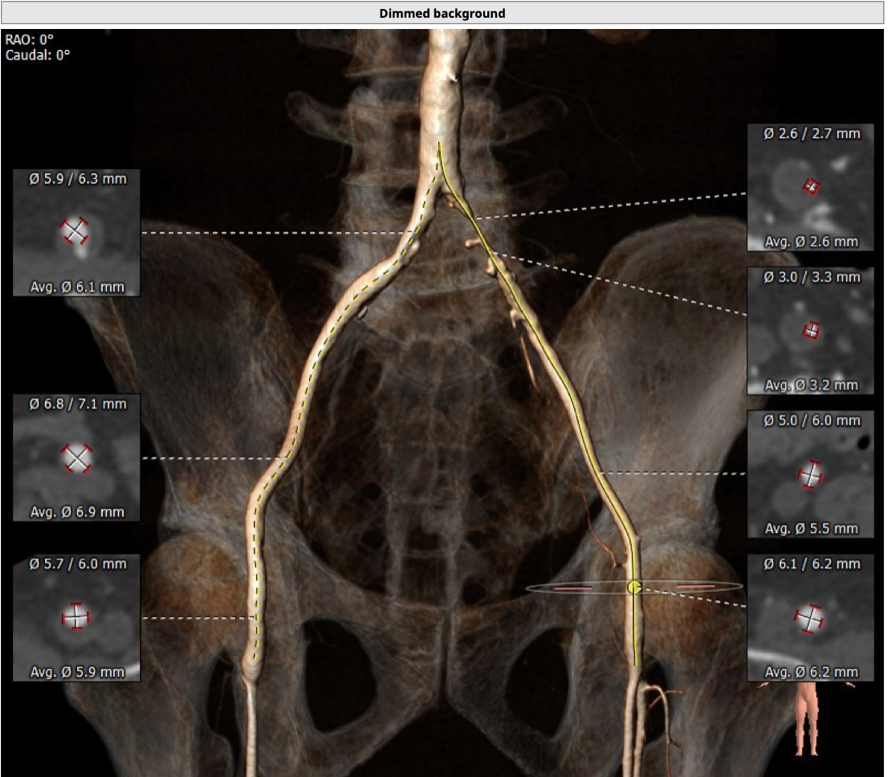

患者为73岁老年男性。CT评估显示其为三叶瓣,伴有轻度钙化,双冠高度可,升主动脉未见明显增宽,主动脉弓部角度平缓。瓣环最短径为17.6mm,最长径为24.7mm,平均瓣环直径为21.1mm。升主动脉平均直径33.6mm。左冠开口高度12.0mm,右冠开口高度14.2mm,冠脉阻塞风险低。外周血管未见明显钙化,最窄处直径为5.7mm。入路情况较佳。

外周血管入路